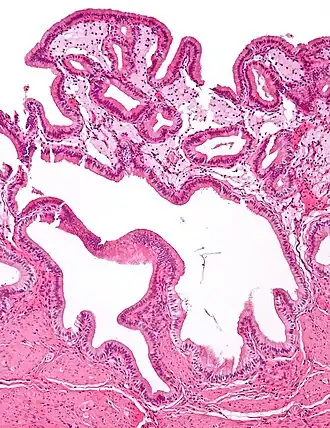

Micrograph of cholesterolosis of the gallbladder -

Micrograph of cholesterolosis of the gallbladder